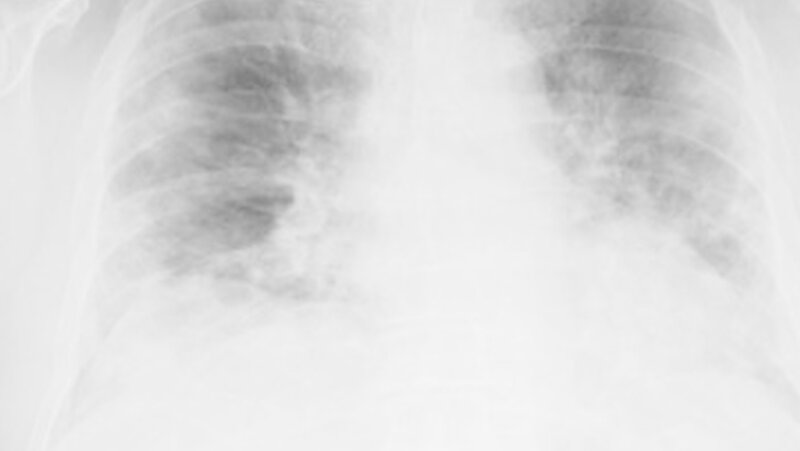

Das neu identifizierte Coronavirus SARS-CoV-2 verursacht die "Corona virus disease 2019" (Covid-19) und ist Auslöser der COVID-19-Pandemie.